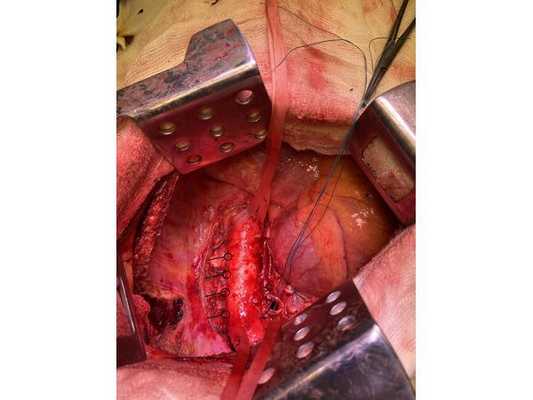

Интраоперационное фото: клипированные межрёберные артерии; аорта на тесёмочных держалках по краям зоны резекции адвентиции; культя главного бронха с провизорными швами при ушивании по Оверхольту

1. В положении на правом боку с раздельной вентиляцией лёгких выполнена боковая торакотомия слева. При ревизии:

Учитывая данные интраоперационной ревизии, диагноз скорректирован: центральный местно-распространённый немелкоклеточный рак нижней доли левого лёгкого с врастанием в адвентицию аорты и ткани средостения — cT4NxM0. Принято решение о выполнении пневмонэктомии (полного удаления лёгкого).

2. Выделены и взяты на держалки верхняя и нижняя лёгочные вены, выделен ствол лёгочной артерии, который также взят на держалку. Выполнено пробное пережатие лёгочной артерии — нарушений гемодинамики (движения крови по сосудам) и гемоксигенации (насыщения крови кислородом) нет.

3. Последовательно прошиты сшивающими аппаратами и пересечены нижняя и верхняя лёгочные вены и ствол лёгочной артерии. Выявлено, что опухоль подрастает к мышечной стенке пищевода, выполнена краевая резекция мышечной стенки пищевода на протяжении 2 см.

4. Острым путём отсечён левый главный бронх, при этом обнаружено, что опухоль распространяется перибронхиально. Культя левого главного бронха реампутирована (ампутирована повторно) в пределах визуально здоровой ткани стенки бронха, до 1,5-2 см от карины трахеи (гребня хряща между разделением двух главных бронхов). Центральная часть культи левого главного бронха ушита по Оверхольту.

5. Отступив по грудной стенке от края врастания опухоли в аорты на 2 см, рассечена и отсепарована (отделена хирургически) париетальная плевра и адвентиция аорты. Аорта мобилизована по типу "ручки чемодана" и взята на тесёмочные держалки выше и ниже места врастания опухоли.

6. Скелетизируя грудную стенку и аорту, с перевязкой левых межрёберных артерий, на участке рёбер 4, 5, 6 и 7 выполнена полуциркулярная резекция адвентиции аорты, мягких тканей грудной стенки с париетальной плеврой и тканей средостения.

7. Пневмонэктомия. Проверка аэростаза (герметичности) под уровнем жидкости — просачивания воздуха в области культи бронха нет.